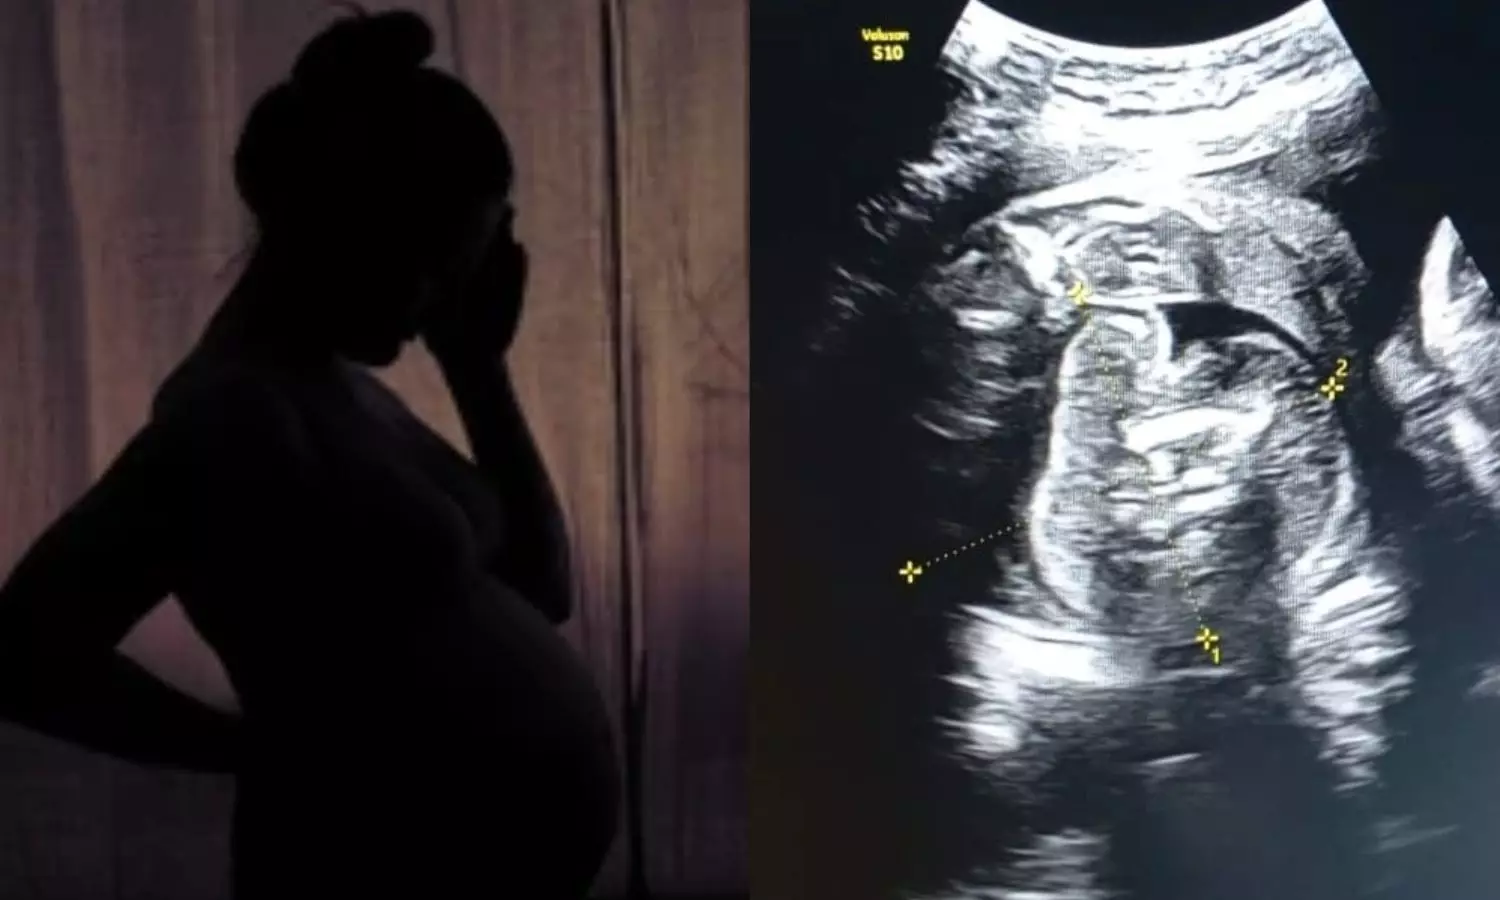

கர்ப்பிணிப் பெண்ணின் வயிற்றில் உள்ள குழந்தைக்குள்... ... இன்றைய முக்கிய செய்திகள்.. லைவ் அப்டேட்ஸ்